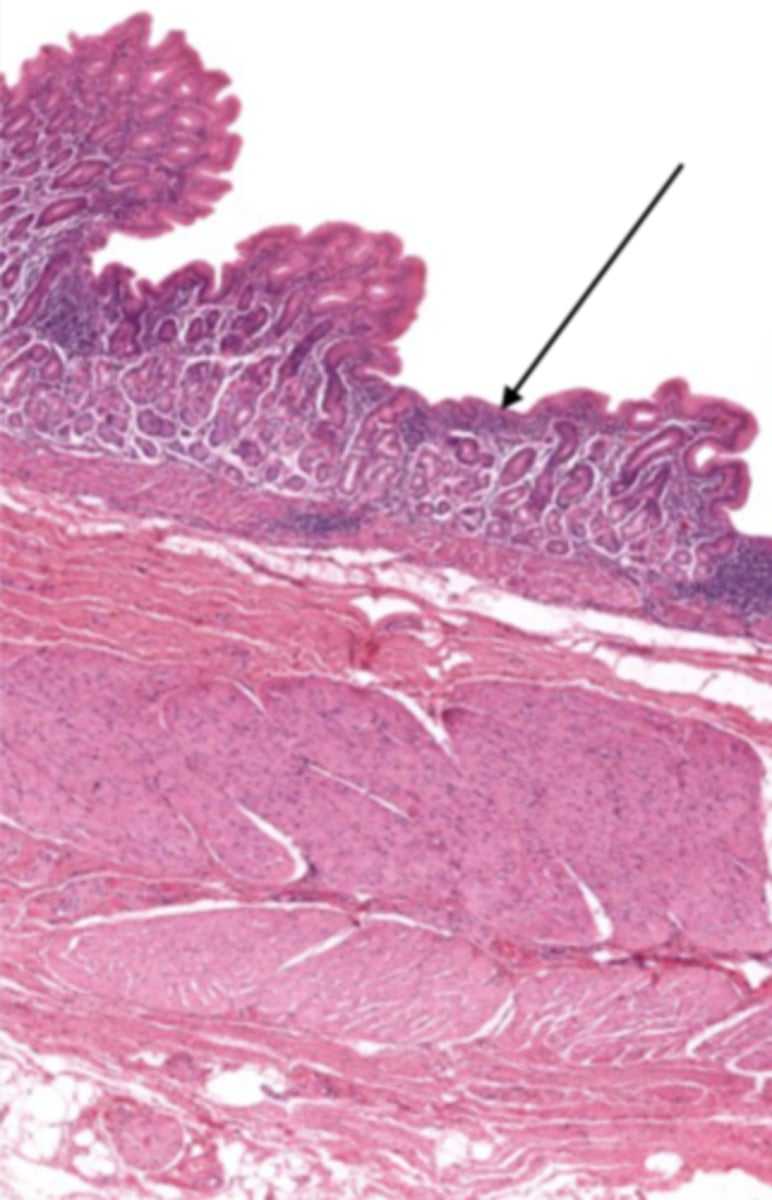

cardiac stomach (histology)

simple columnar epithelium

what kind of epithelium lines the mucosa of the cardiac stomach?

gastric pit (cardiac stomach)

lumen (cardiac stomach)

mucosa (cardiac stomach)

mucosal epithelium (cardiac stomach)

lamina propria (cardiac stomach)

muscularis mucosa (cardiac stomach)

submucosa (cardiac stomach)

contains glands and blood supply

muscularis externa (cardiac stomach)

serosa/adventitia (cardiac stomach)